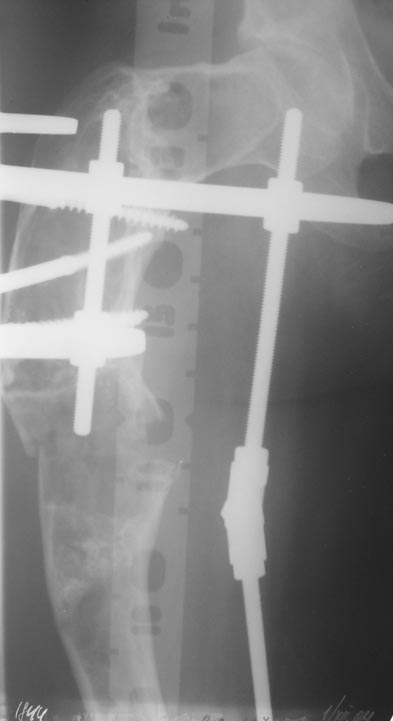

Уважаемые коллеги! Большое спасибо за живой отклик и предложения по тактике лечения. Больной произведен первый этап - стержневой аппарат издвух баз, кортикотомия, остеоклазия и начата коррекция в аппарате. Почти исправлен угол, не сегодня укорочение 2см. Когда завершим коррекция, представлю рентгенограммы.

Re: Деформация бедра

Leonid Pollyak 02 Январь 2005, 22:42

В ноябре этого года я обращался с просьбой о помощи в выборе тактики лечения больной с деформацией бедра на почве фиброзной дисплазии. Были получены интересные и очень полезные советы по операции.

Хотелось бы показать, что получилось в результате.

Операция выполнялась с помощью А.Н.Челнокова. Очень понравилась технология выполнения блокируемого остеосинтеза с использованием спицевого дистрактора, модифицированный гвоздь с латерализованным проксимальным отделом и возможностью многовинтовой фиксации проксимального и дистального участков бедра.